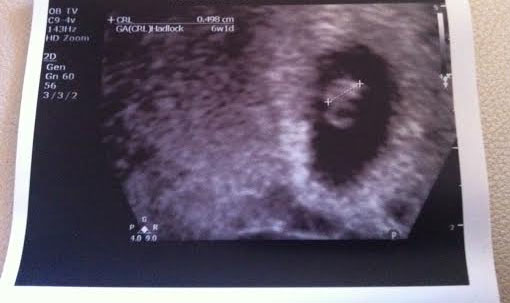

We had our 1st Ultrasound scan last friday, in my 6th week. Was really nervous on that day.

But all went well when we went for the Ultrasound Scan.

We did a trans vaginal scan and it was a bit painful. Doctor said the uterus area is very sensitive right now, which explains why it’s uncomfortable.

When i saw the flicker, i knew it was the heartbeat and i was overwhelmed with happiness.

I have a baby. A baby with a heartbeat. So so relieved.

Yes, we’re expecting a singleton! You know when we 1st did the transfer, i was hoping for twins. That would be really awesome. But nearer to the scan date, i think with all the jitters and all, i was hoping for a singleton.